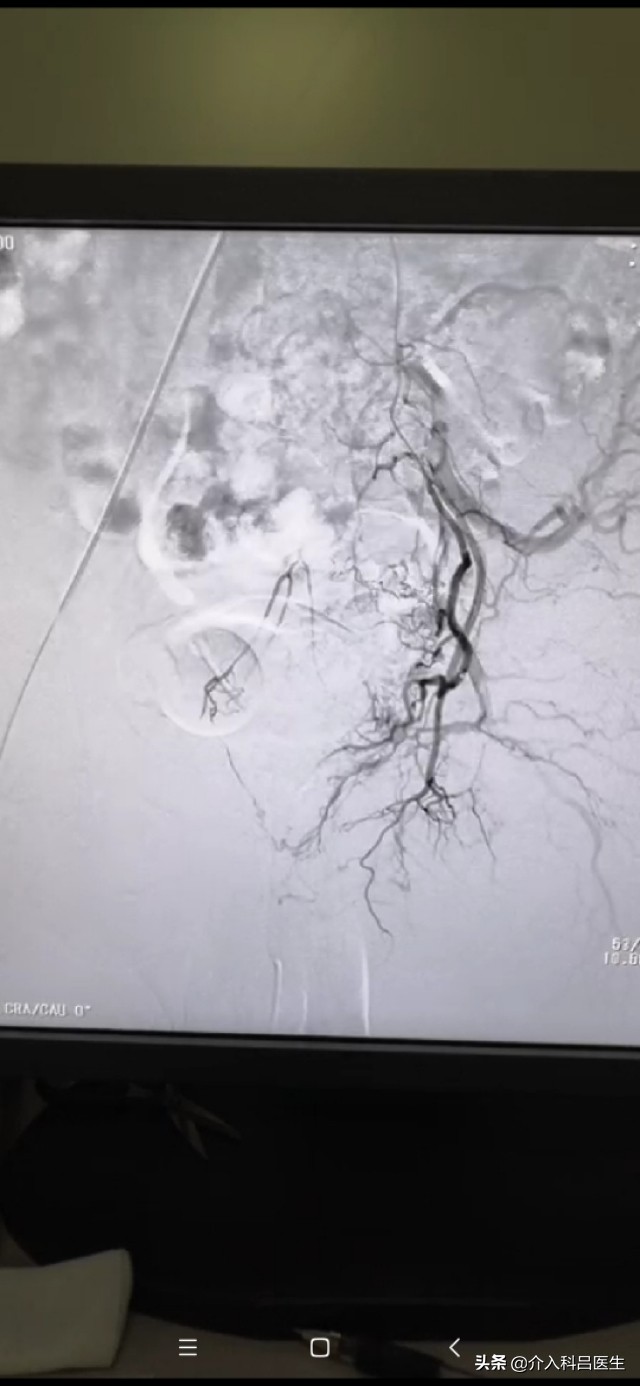

这是一种超选择性子宫腺肌症血管床栓塞术,经皮穿刺将1 毫米~2 毫米粗的导管送入子宫动脉,使导管尽可能接近病理血管床,经导管注射微小的球形栓塞剂,以栓塞病灶的末梢血管网,使子宫腺肌症组织因缺血、缺氧而坏死,坏死的物质通过淋巴与静脉血管网的吸收而被清除。子宫腺肌症的异位子宫内膜具有激素依赖性,阻断其供血也就阻断了激素作用,发挥双重治疗作用。